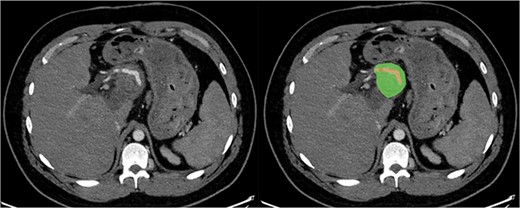

Subsequently, the patient developed severe abdominal pain and a computed tomography (CT) demonstrated possible impending perforation of the teratoma. Emergency laparotomy was performed. The teratoma was found posterior to the neck of the pancreas extending retroperitoneally behind the lesser sac. The portal structures and pancreas were attenuated and stretched over the lesion. Both the superior mesenteric vein (SMV) and inferior mesenteric vein were densely adherent to the teratoma. The superior mesenteric artery (SMA) was not able to be visualized (Fig. 1). An initial attempt was made at resection of lesion. However, when beginning to mobilize the lesion it was felt that, in order for a complete resection, at least a total pancreatectomy with portal vein reconstruction was to be required. However, due to the fact that it may not be possible to resect the lesion from the SMA or the possibility that the portal vein and SMV could not be anastomosed, radical resection was abandoned. Instead, a debulking of the mass was performed with drainage of perforated cystic contents from the abdomen.

Sagittal section of pre-operative CT with portal venous contrast showing the lesions relationship to major vascular structures of the abdomen. Labels: ^ - fistula opening, blue # - superior mesenteric vein, blue * - inferior vena cava, red - superior mesenteric artery.